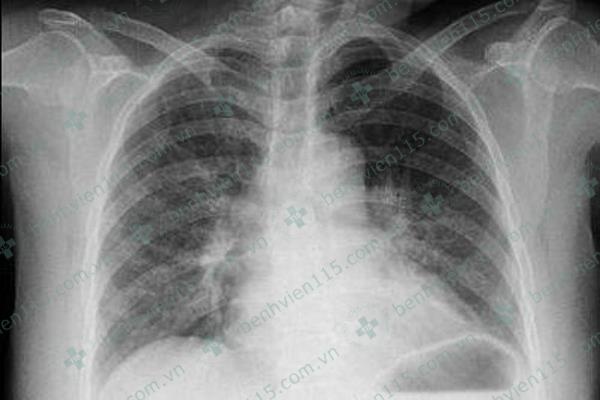

| Hình ảnh chụp X-quang tim phổi thẳng của bệnh nhân. Ảnh: BVCC |